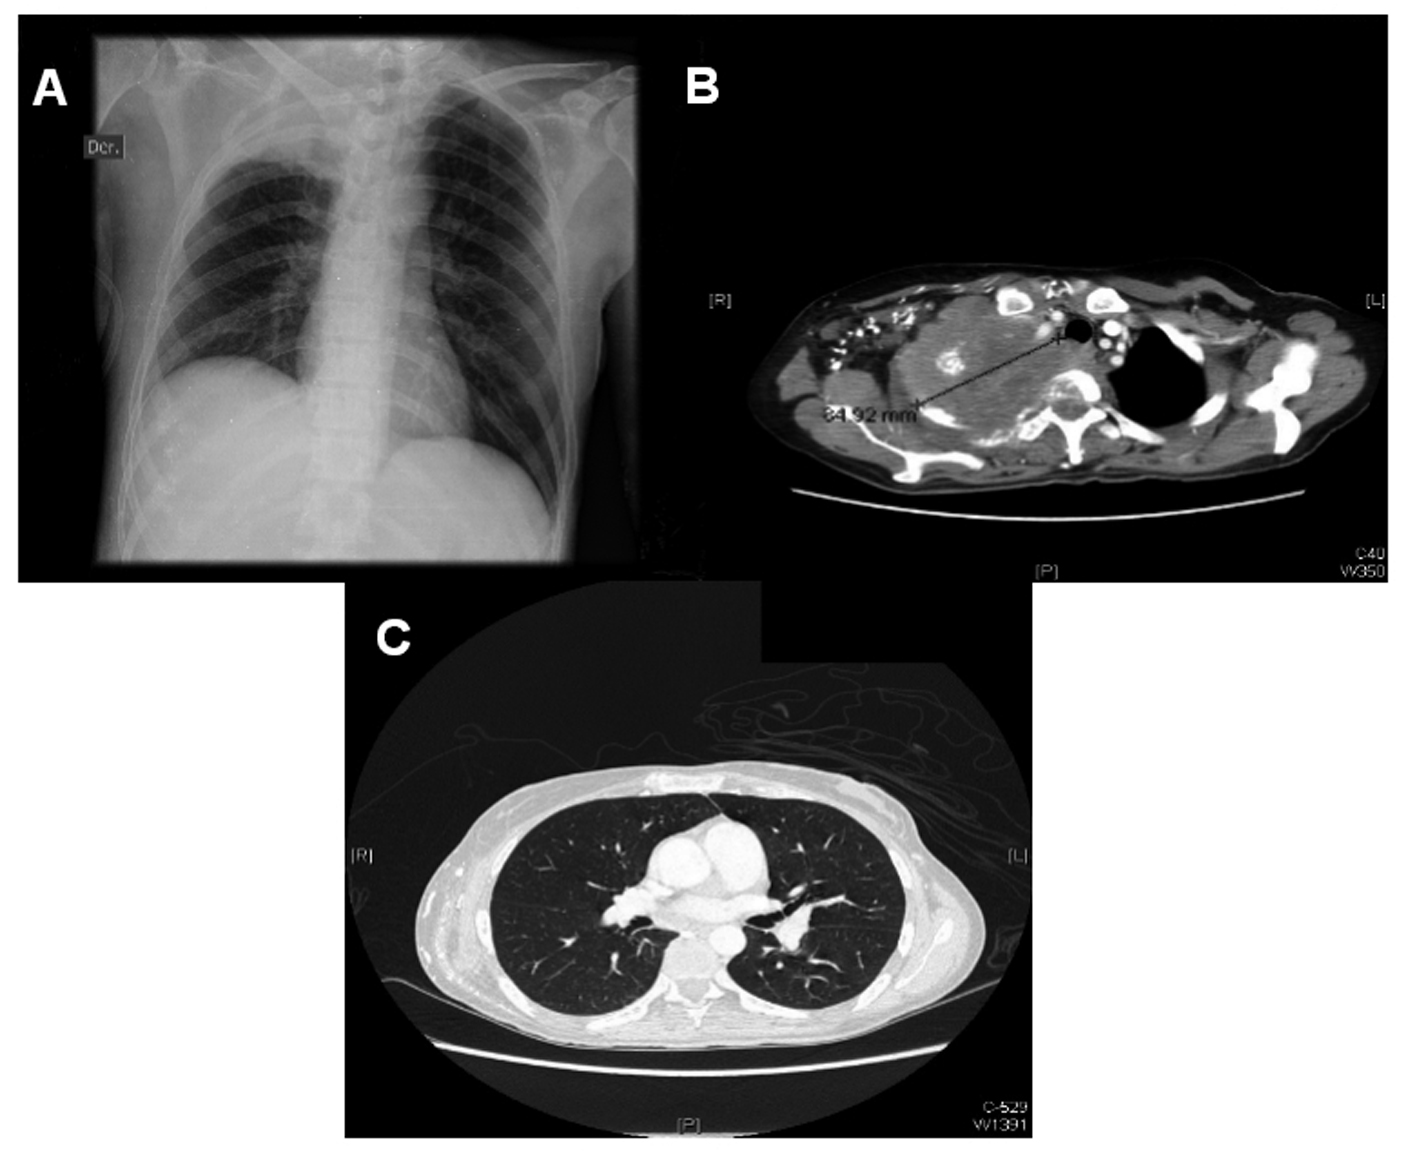

A 40 years old patient with a history of stage IIIb espinocellular cervical cancer diagnosed in 2008 and treated with radiotherapy presented with a history of a right supraclavicular mass that had been growing in the last three months. Four days before her admission, the patient presented sudden paraparesis and bladder incontinence. The neurological exploration also revealed right eye ptosis and a myotic pupil. She also reported weight loss and malaise in the preceding weeks. Her electrolytes, blood chemistries, liver function tests and blood count were normal, except for mild hypoalbuminemia and normocytic anemia. A chest radiograph showed a condensation suggesting a mass in her right lung, without other nodules or widened mediastinum. A chest computer tomography (CT) was ordered, with the finding of a large pulmonary mass invading the thoracic vertebrae (Fig. 1). The patient was immediately started on steroids and local radiotherapy, and a biopsy later showed the mass to be cervical cancer metastasic disease. She had mild clinical improvement.

![]() Click for large image | Figure 1. Chest x-ray showing right apical opacity (A). Chest CT showing large apical lung mass, invading vertebral body (B). Rest of lung parenchima is intact, there is no hilar adenopathy (C). |